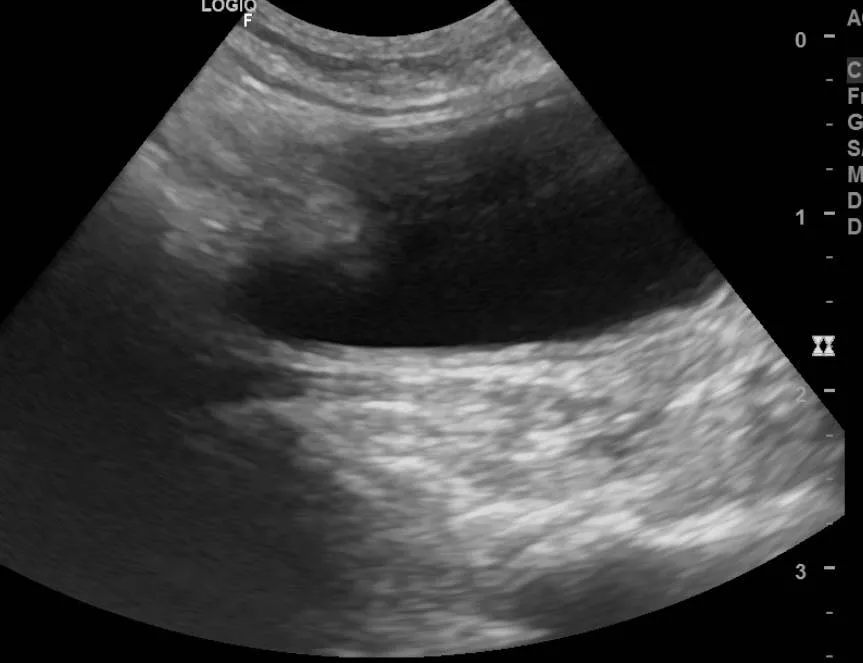

橘白小貓小虎突然肚子鼓鼓的,飼主以為是變胖,結果發現牠精神差、食慾不好,到院後一照超音波,腹腔裡滿滿的腹水!

抽出的腹水呈黃色黏稠,血檢球蛋白很高——高度懷疑是傳染性腹膜炎(FIP)。

橘白小貓小虎突然肚子鼓鼓的,飼主以為是變胖,結果發現牠精神差、食慾不好,到院後一照超音波,腹腔裡滿滿的腹水!

抽出的腹水呈黃色黏稠,血檢球蛋白很高——高度懷疑是傳染性腹膜炎(FIP)。